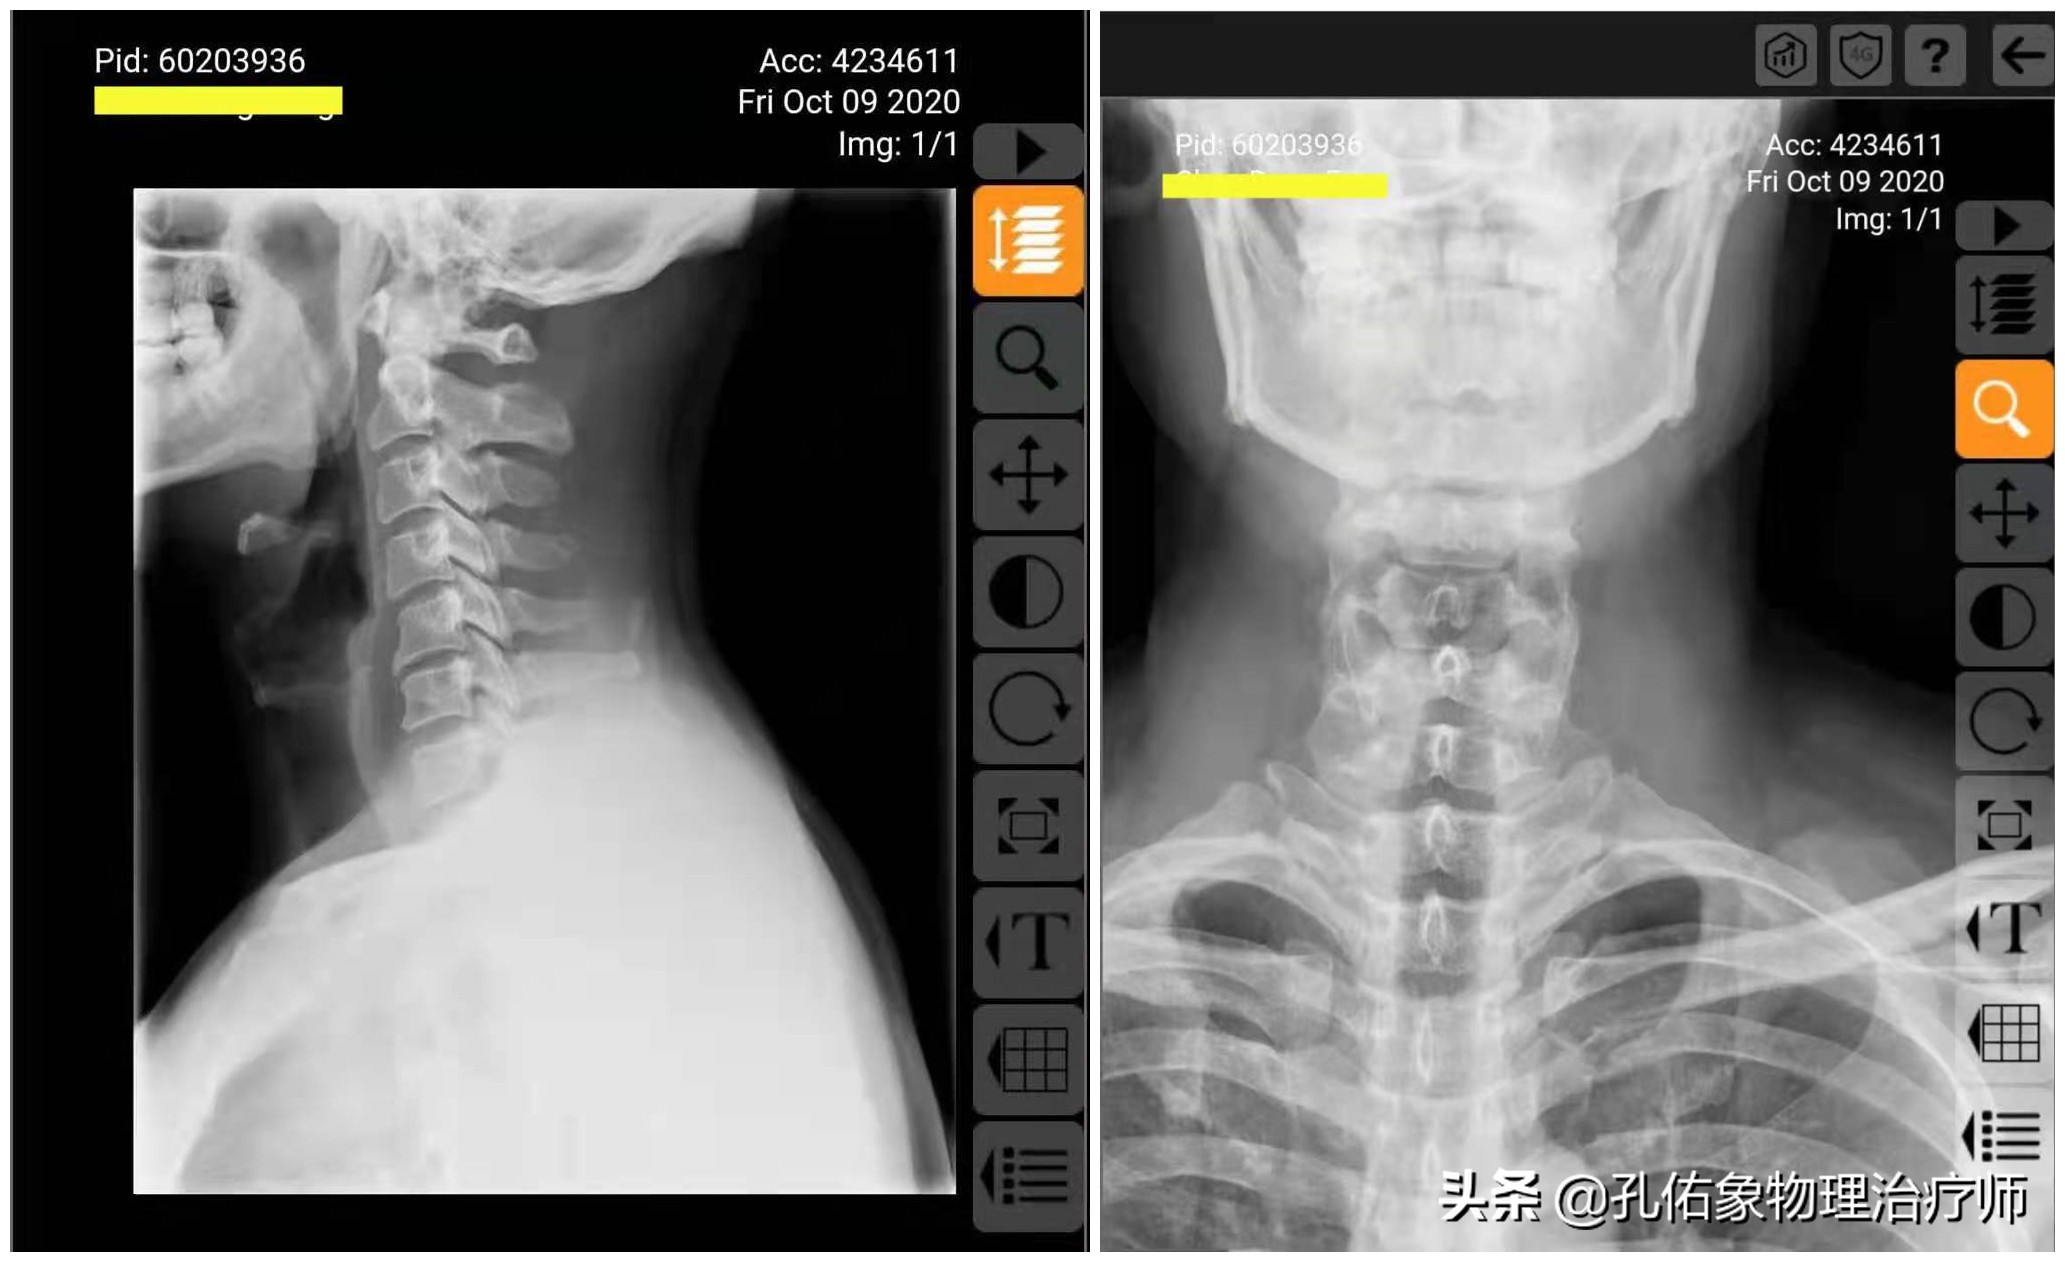

在患有颈椎问题时,出现症状,被要求拍片子后,我们拿到手的报告单通常会显示这样的字样:颈椎退行性改变、颈椎生理曲度变直、颈椎骨质增生、椎间隙变窄等。如下图所示:

颈椎正、侧位片

上图所示的片子,是一位颈痛患者的正、侧位X片,影像科拍片大夫的报告单中是这样写的:

一般在报告单的下方,都会有 此报告为影像诊断,仅供临床医生参考,请结合临床 的字样。意思就是告诉您,报告显示的仅是影像诊断,而不是临床诊断;可我们很多患者都会有这样的习惯:拿到片子报告后,显示什么就认为是什么,然后拿着报告单就问,医生我颈椎退变、骨质增生,应该怎么治疗?

上文中的颈椎正侧位X片,在影像科大夫和非专业的人眼睛里,它反应的是颈椎问题,但对于治疗的人员,真没有治疗性的指导作用。

在专业治疗人员这,会重新分析解读颈椎的正侧位X片:

片子读完之后,可以详细得知该片子的患者主要颈椎问题是发生在第5颈椎,有骨质增生,椎体发生向后、向右、向下的错位,而第6、7颈椎发生向后、向左、向下的错位。这样就可以判断出颈6、颈7神经有卡压情形,结合相应神经支配区查体,两者是否吻合,再给予徒手治疗。

治疗的原则:主要针对有问题的椎体节段给予反方向调整;关节排列紊乱错位,就如同拧螺帽一样,太松了就顺时针拧一拧,太紧了就逆时针松一松,只要诊断明确,给予病灶椎的椎板反方向调整,可以收到立竿见影的效果。